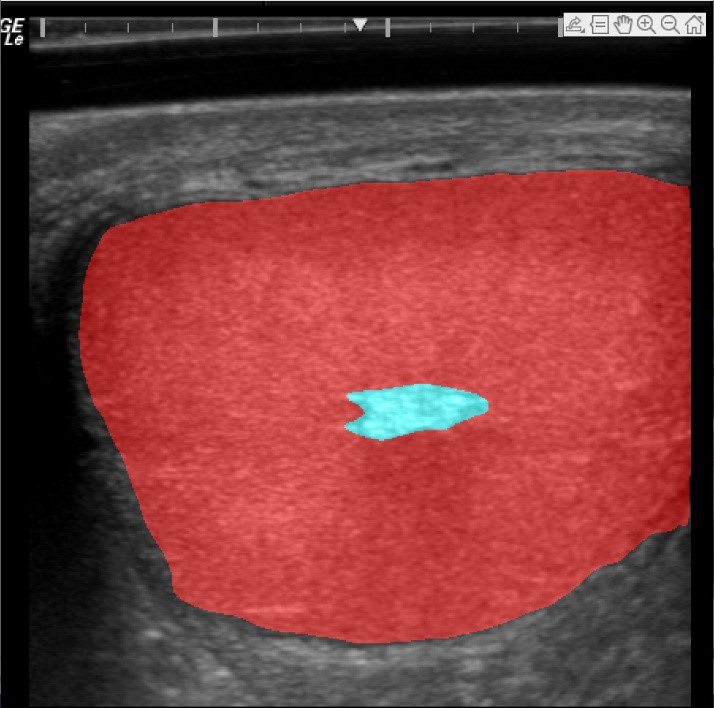

Die neu entwickelte Fertiboar Technologie basiert auf der Analyse von Ultraschall-Bildern der Eberhoden. Diese geben Aufschluss über die Eigenschaften des Spermien-produzierenden Gewebes (Theriogenologie 158 (2020): Pp 58-65). Mit Hilfe von Machine Learning (Convolutional Neural Network) wurden die Regionen, die für die Samenproduktion entscheidend sind, innerhalb der Hodenbilder automatisiert identifiziert. Diese Regionen wurden analysiert, um Parameter zu berechnen, die Attribute wie Homogenität und Echogenität des Gewebes beschreiben.

In einem zweiten Schritt wurde ein Supervised Learning Algorithm auf die berechneten Parameter angewendet, um die Wahrscheinlichkeit vorherzusagen, dass ein Eber Ejakulate von gewünschter Qualität produziert. Durch laufende Erfassung von Ultraschall-Daten und die Rückmeldung der zugehörigen Spermaqualitätsparameter durch die Besamungsstationen wird die Vorhersagekraft dieser innovativen Technologie kontinuierlich verbessert und wird PIC helfen, die Qualität ihrer Produkte weiter zu erhöhen.